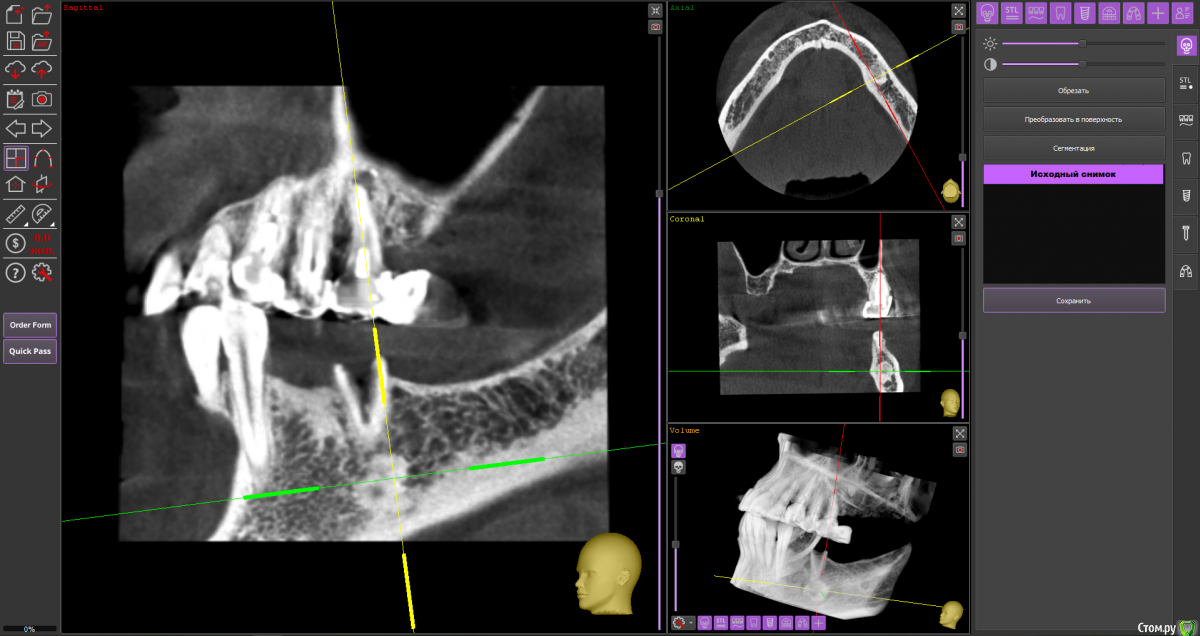

almaz7888 Опубликовано 11 февраля, 2021 Поделиться Опубликовано 11 февраля, 2021 (изменено) Доброе утро коллеги! Подниму тему. Данной пациентке планируется имплантация для замещения концевых дефектов на нижней челюсти. Зуб 3.5 думал удалить во время операции. Образование в области 3.5 это просто склероз кости? В области ментального отверстия справа также имеется какой-то очаг но меньших размеров. Изменено 11 февраля, 2021 пользователем almaz7888 Ссылка на комментарий